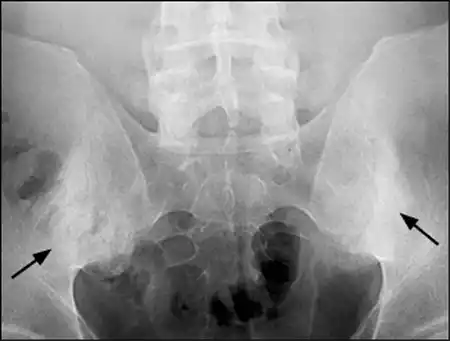

| Radiographic Findings | Bamboo spine (fusion of vertebrae), sacroiliitis (inflammation of sacroiliac joints). | Joint erosions, periarticular bone proliferation (“pencil-in-cup” deformity). |

- X-rays: X-rays of the spine and sacroiliac joints may reveal characteristic findings, such as bamboo spine (fusion of vertebrae) or sacroiliitis (inflammation of the sacroiliac joints).

- X-rays: X-rays of affected joints may show joint erosions or periarticular bone changes, which are indicative of PsA.